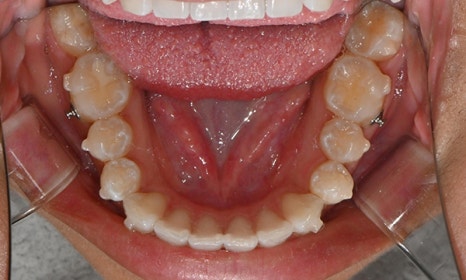

위아래 앞니 사이가 벌어져서 공간이 있었고, 앞니에 약간씩 배열이 틀어진 덧니가 있었습니다. 정면에서 보았을 때 윗니와 아래 앞니가 깊게 물려서 아래 앞니가 잘 보이지 않는 과개교합 양상을 보이고 있었습니다. 또한 왼쪽 아래 작은 어금니가 90도 앞으로 돌아가서 좌측 치아 배열 및 교합이 좋지 않은 상태였습니다.

초진시 구내사진 (2025. 3.31)